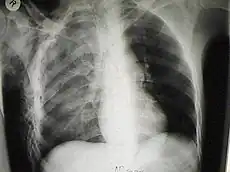

Traumatismo de tórax

Un traumatismo torácico es una lesión grave en el tórax, bien sea por impactos de golpes contusos o por heridas penetrantes. El traumatismo torácico es una causa frecuente de discapacidad y mortalidad significativa, la principal causa de muerte después de un trauma físico a la cabeza y lesiones de la médula espinal.

Los traumatismos torácicos pueden afectar a la pared ósea del tórax, la pleura y los pulmones, el diafragma o el contenido del mediastino. Debido a potenciales lesiones anatómicas y funcionales de las costillas y de tejidos blandos incluyendo el corazón, pulmón o grandes vasos sanguíneos, las lesiones torácicas son Emergencias médicas que si no son tratadas rápida y adecuadamente pueden dar como resultado la muerte.